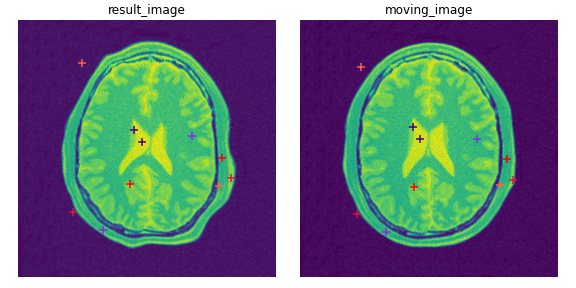

得られたfixed空間の点群result_pointsをplotすると以下のようになります.

画像変形による点群の対応を確認することができました.